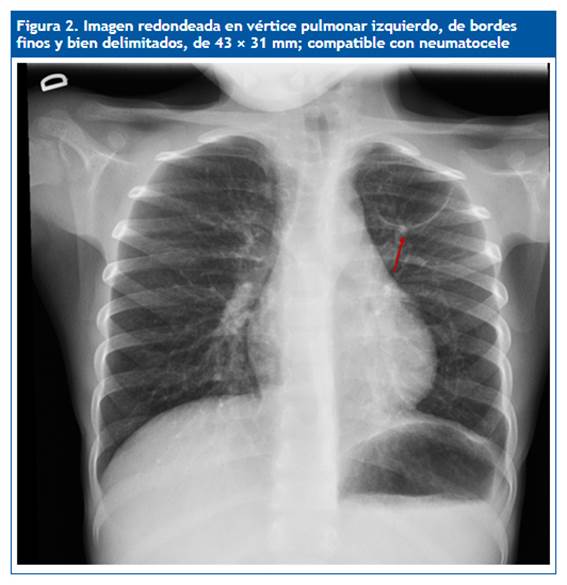

En la revisión 50 días más tarde se aprecia la resolución completa de la consolidación neumónica y una imagen elíptica de 4,3 × 3 cm en el vértice superior izquierdo compatible con neumatocele (Fig. 2). Se opta por tratamiento conservador. En una nueva placa realizada tres meses después se observa una imagen similar, y cuatro meses más tarde (nueve tras diagnóstico inicial) se aprecia, en la radiología torácica convencional, la desaparición de la imagen previa, lo que demuestra resolución espontánea y confirma la sospecha inicial de neumatocele.